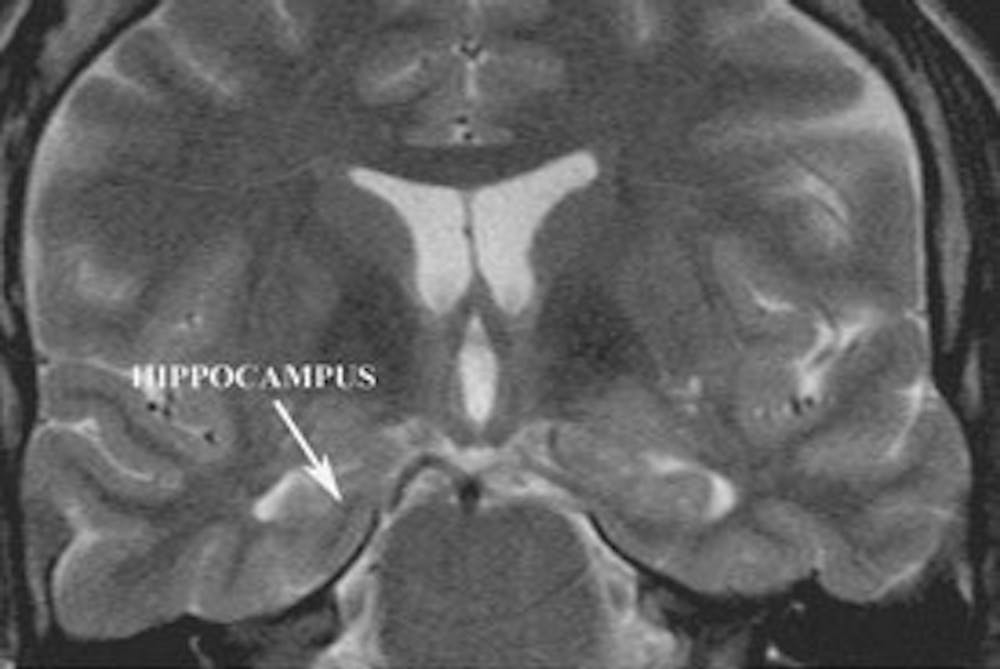

ए) क्लासिक टेम्पोरल लोब मिर्गी के रोगी में दौरे की गतिविधि (हिप्पोकैम्पस) की उत्पत्ति को प्रदर्शित करने वाला कोरोनल टी2 भारित एमआरआई